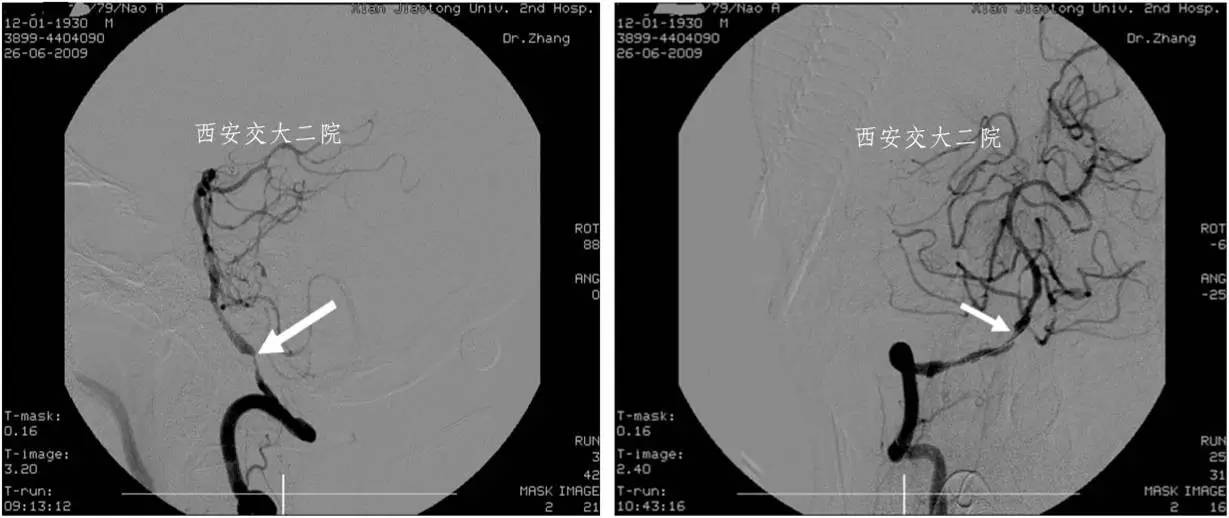

Case 1 颈内动脉C1段急性闭塞(2009年)

》男,70岁,突发右侧肢体无力3小时,DSA提示左侧颈内动脉起始段闭塞。

Case 2 左侧大脑中动脉溶栓+支架 (2009年)

》男,44岁,突发言语不能,右侧肢体活动不灵2小时。

》尿激酶10万后MCA未通,给予Apollo支架植入。